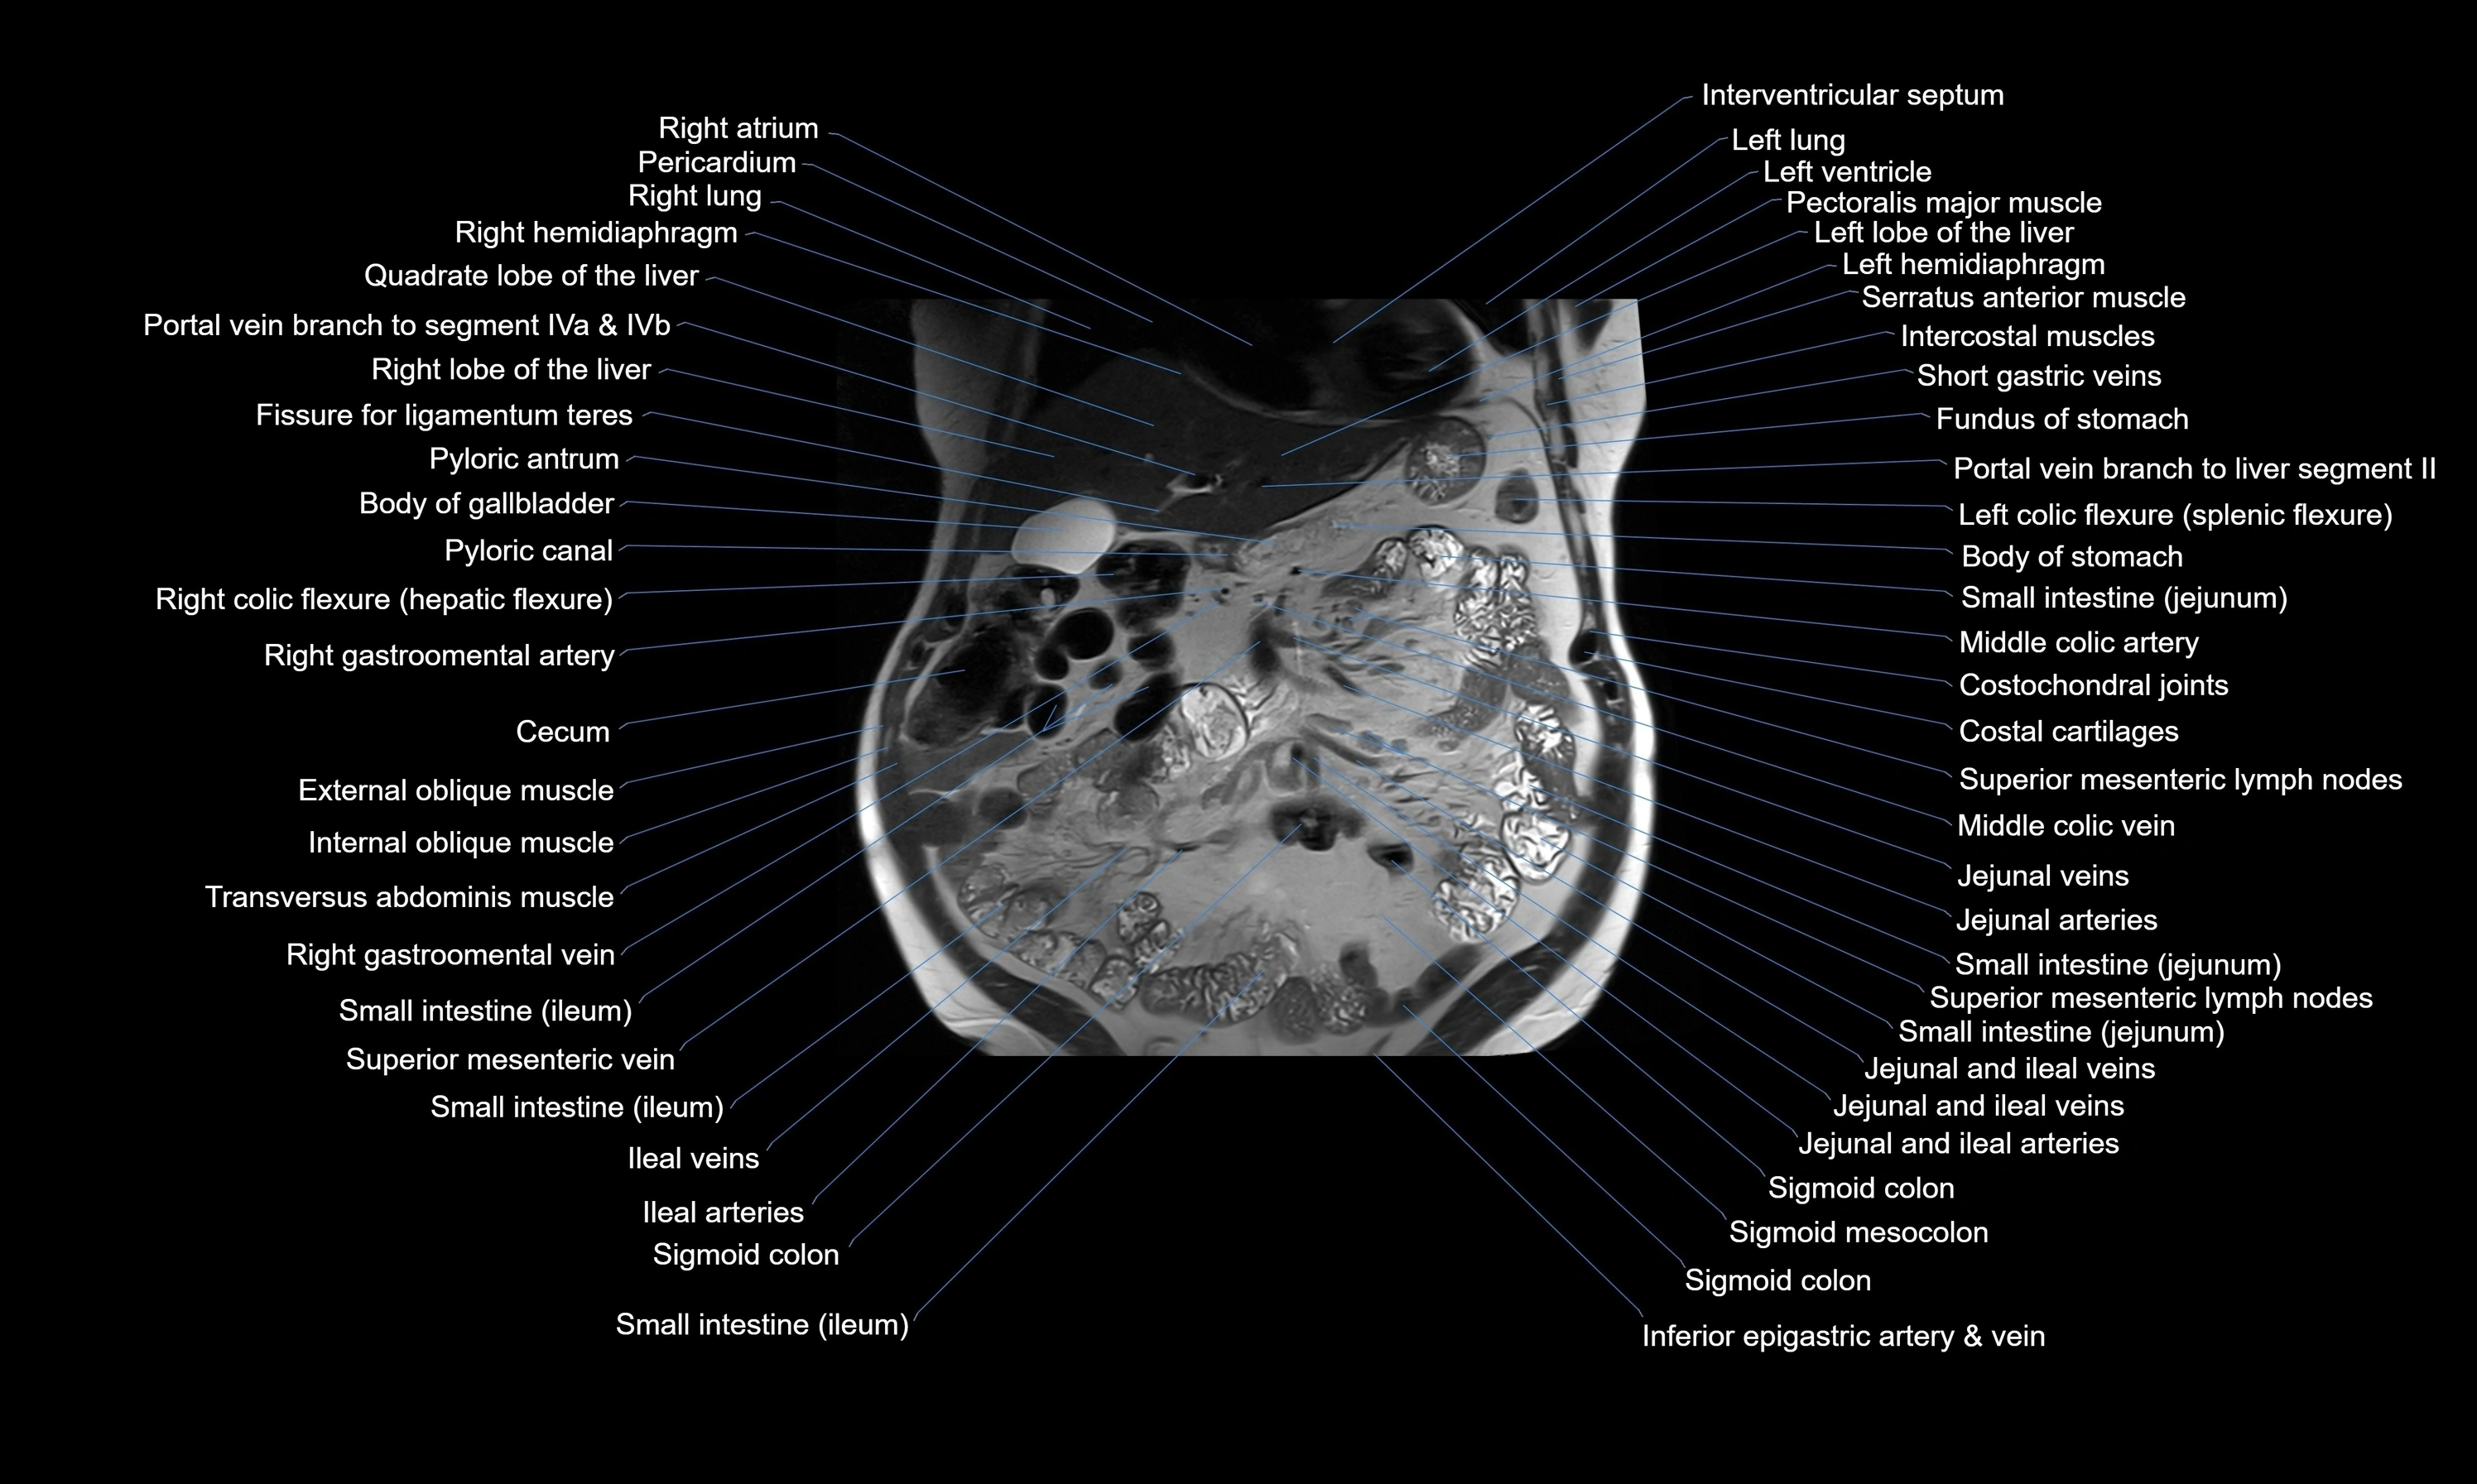

- Liver

- Stomach

- Gallbladder

- Cecum

- Jejunum

- Ileum

- Superior mesenteric lymph nodes